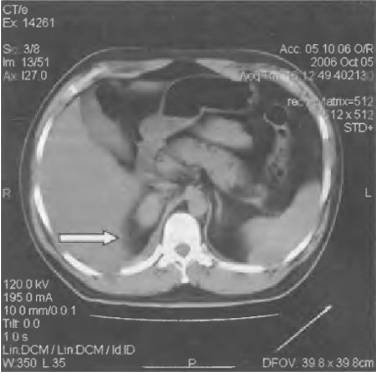

- компьютерной томографии;

- исследования газового состава крови;